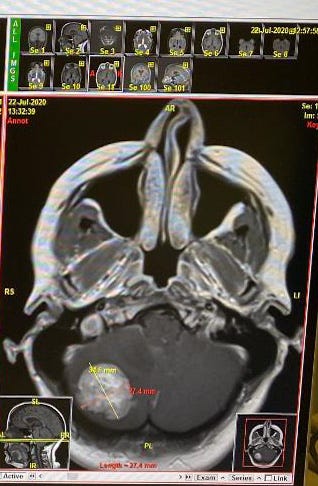

I just talked to the Neurosurgeon and everything went great with the surgery. He was able to remove the tumor intact! He is 99.9% sure it is the evil Breast cancer that spread to her cerebellum. He sent some of it off to Pathology for confirmation. I should get to see Renee in about an hour for only a couple of minutes before she goes back to her room. He thinks she can be released from hospital on Saturday or Sunday, but we can’t leave Atlanta for 4-5 days just to be safe. Yay, we are staying in hotel in Atlanta during COVID!!!